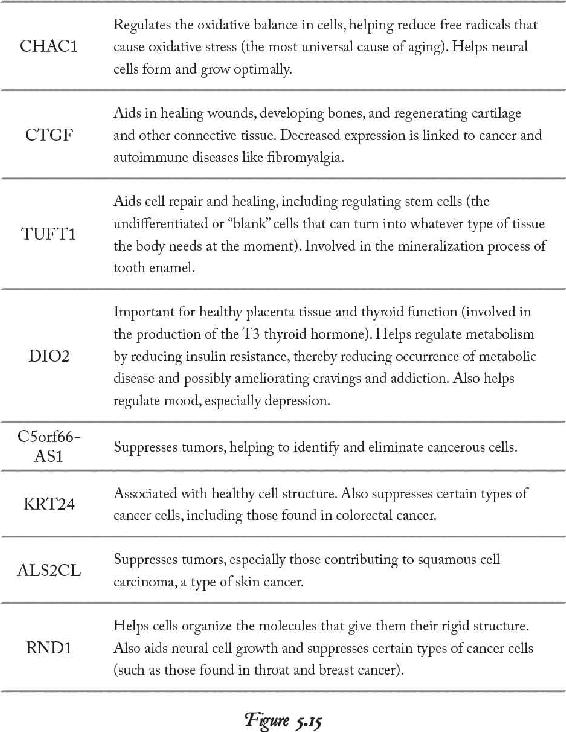

We know it’s true because our studies show significant changes in our students’ gene expression, and they’ve then reported significant changes in their health. Once we can show someone measurable results proving they truly have altered neurotransmitters, hormones, genes, proteins, and enzymes through thought alone, they can better justify their efforts and prove to themselves that they really are transforming.

I’ll give you the physiology of the breath so you can put more intention behind it when you begin to free yourself from the past. Once you start to liberate all that energy back into the brain, then you will learn how to recondition your body to a new mind. I’m going to show you how to teach your body emotionally how to live in the future-present reality instead of the past-present reality where we spend most of our time. Science tells us that the environment signals the gene. Since emotions are the chemical end products of experiences in our environment, when you embrace elevated emotions in your meditations, you will not only raise your body’s energy, but you will also start to signal new genes in new ways—ahead of the environment.

Since Anna also studied the model of epigenetics I teach in our workshops and lectures, she learned that genes don’t create disease; instead, the environment signals the gene to create disease. Anna understood that if her emotions were the chemical consequences of experiences in her environment, and if she lived every day by the same emotions from her past, she was selecting and instructing the same genes that might be causing her poor health conditions. If she could instead embody the emotions of her future life by embracing those emotions before the experience actually happened, she could change her genetic expression and actually change her body to be biologically aligned with her new future.